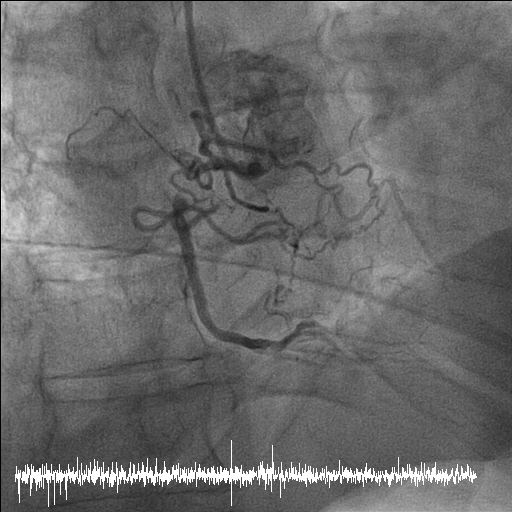

Coronary angiography disclosed orifice total occlusion with TIMI grade 0 antegrade flow at LAD, middle total occlusion at LCX, and RCA proximal total occlusion with auto-collateral to RCA distal.

SCR guiding cath was used to engage RCA. Runthrough wire, Conquest pro, and Conquest 860 wire were used to get cross the CTO lesion. Resolute 2.75x38mm stent was inflated after predilatation with different size BC. XB 3.0x6fr guiding cath was used to engage LCX. Sion blue, Conquest pro, and Fielder XT-A wire were used to get cross the LCX lesion. Predilatation was done with 1.5x20mm BC, followed by Sierra 2.0x38mm stenting and 2.0x30mm B. Braun DEB.

Stage PCI for stumpless LAD-os-P CTO was arranged two months later. Antegrade strategy was tried initially, but shifted to retrograde approach due to wiring failed because of tiny LAD-M true lumen. We used SAL 1x6F guide via right femoral access. After trying, one septal collateral via PDA could be wired with a Fielder XT-R and Caravel. After switching the Caravel to Corsair Pro XS, it could be advanced to LAD-M. The CTO segment was retrogradely attempted with Conquest Pro, UB and finally reached LM body. Using a Sion blue, the wire could go into the antegrade guide, followed by advancing the Corsair Pro XS into the guide. The lesions were antegradely dilated with BC after RG 3 wire externalization and antegrade flow was established. By using a Crusade, the LAD proper could be successfully wired wtih a Fielder XT-A. LAD-M-D and LAD-os-P-M were predilated with a 2x30mm BC(IVUS confirmed all true lumen wiring) and respectively scaffolded with a 2.75x38mm Onyx and a 3x48mm Synergy. There was no residual stenosis over all 3 vessels.

Stage PCI for stumpless LAD-os-P CTO was arranged two months later. Antegrade strategy was tried initially, but shifted to retrograde approach due to wiring failed because of tiny LAD-M true lumen. We used SAL 1x6F guide via right femoral access. After trying, one septal collateral via PDA could be wired with a Fielder XT-R and Caravel. After switching the Caravel to Corsair Pro XS, it could be advanced to LAD-M. The CTO segment was retrogradely attempted with Conquest Pro, UB and finally reached LM body. Using a Sion blue, the wire could go into the antegrade guide, followed by advancing the Corsair Pro XS into the guide. The lesions were antegradely dilated with BC after RG 3 wire externalization and antegrade flow was established. By using a Crusade, the LAD proper could be successfully wired wtih a Fielder XT-A. LAD-M-D and LAD-os-P-M were predilated with a 2x30mm BC(IVUS confirmed all true lumen wiring) and respectively scaffolded with a 2.75x38mm Onyx and a 3x48mm Synergy. There was no residual stenosis over all 3 vessels.